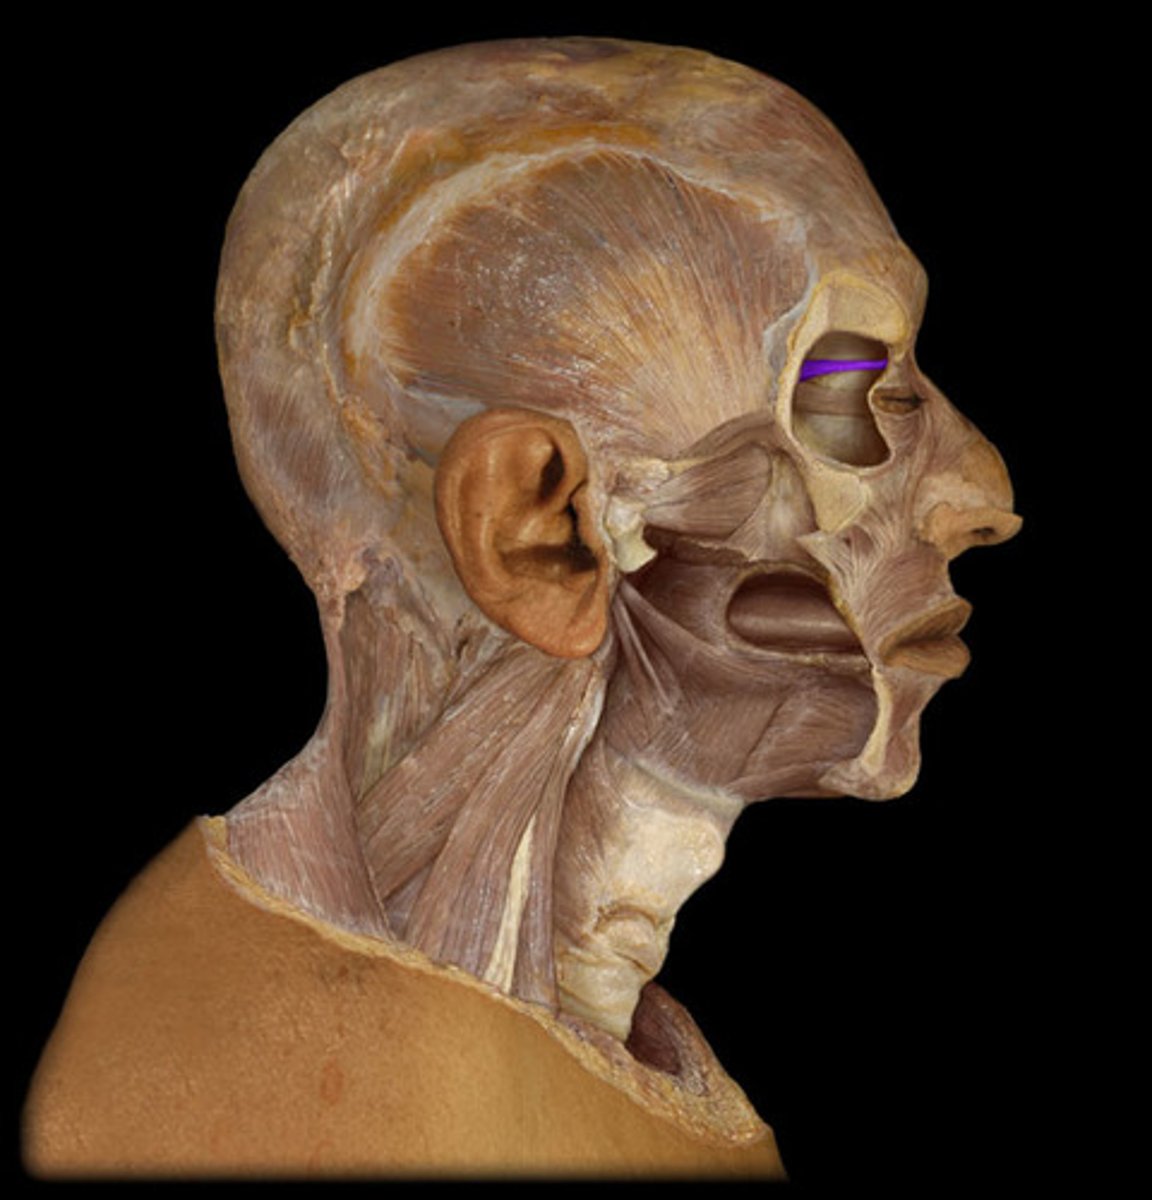

Frontal belly of occipitofrontalis

Occipital belly of occipitofrontalis

Orbicularis oculi

Levator palpebrae superioris

Nasalis

Buccinator

Orbicularis oris

Zygomaticus major

Zygomaticus minor

Levator anguli oris

Levator labii superioris

Depressor anguli oris

Depressor labii inferioris

Mentalis

Platysma

Temporalis

Masseter

Medial pterygoid

Lateral pterygoid

Genioglossus

Styloglossus

Hyoglossus

Medial rectus

Lateral rectus

Inferior rectus

Superior rectus

Inferior oblique

Superior oblique

Sternocleidomastoid

Trapezius

Splenius capitis

Splenius cervicis